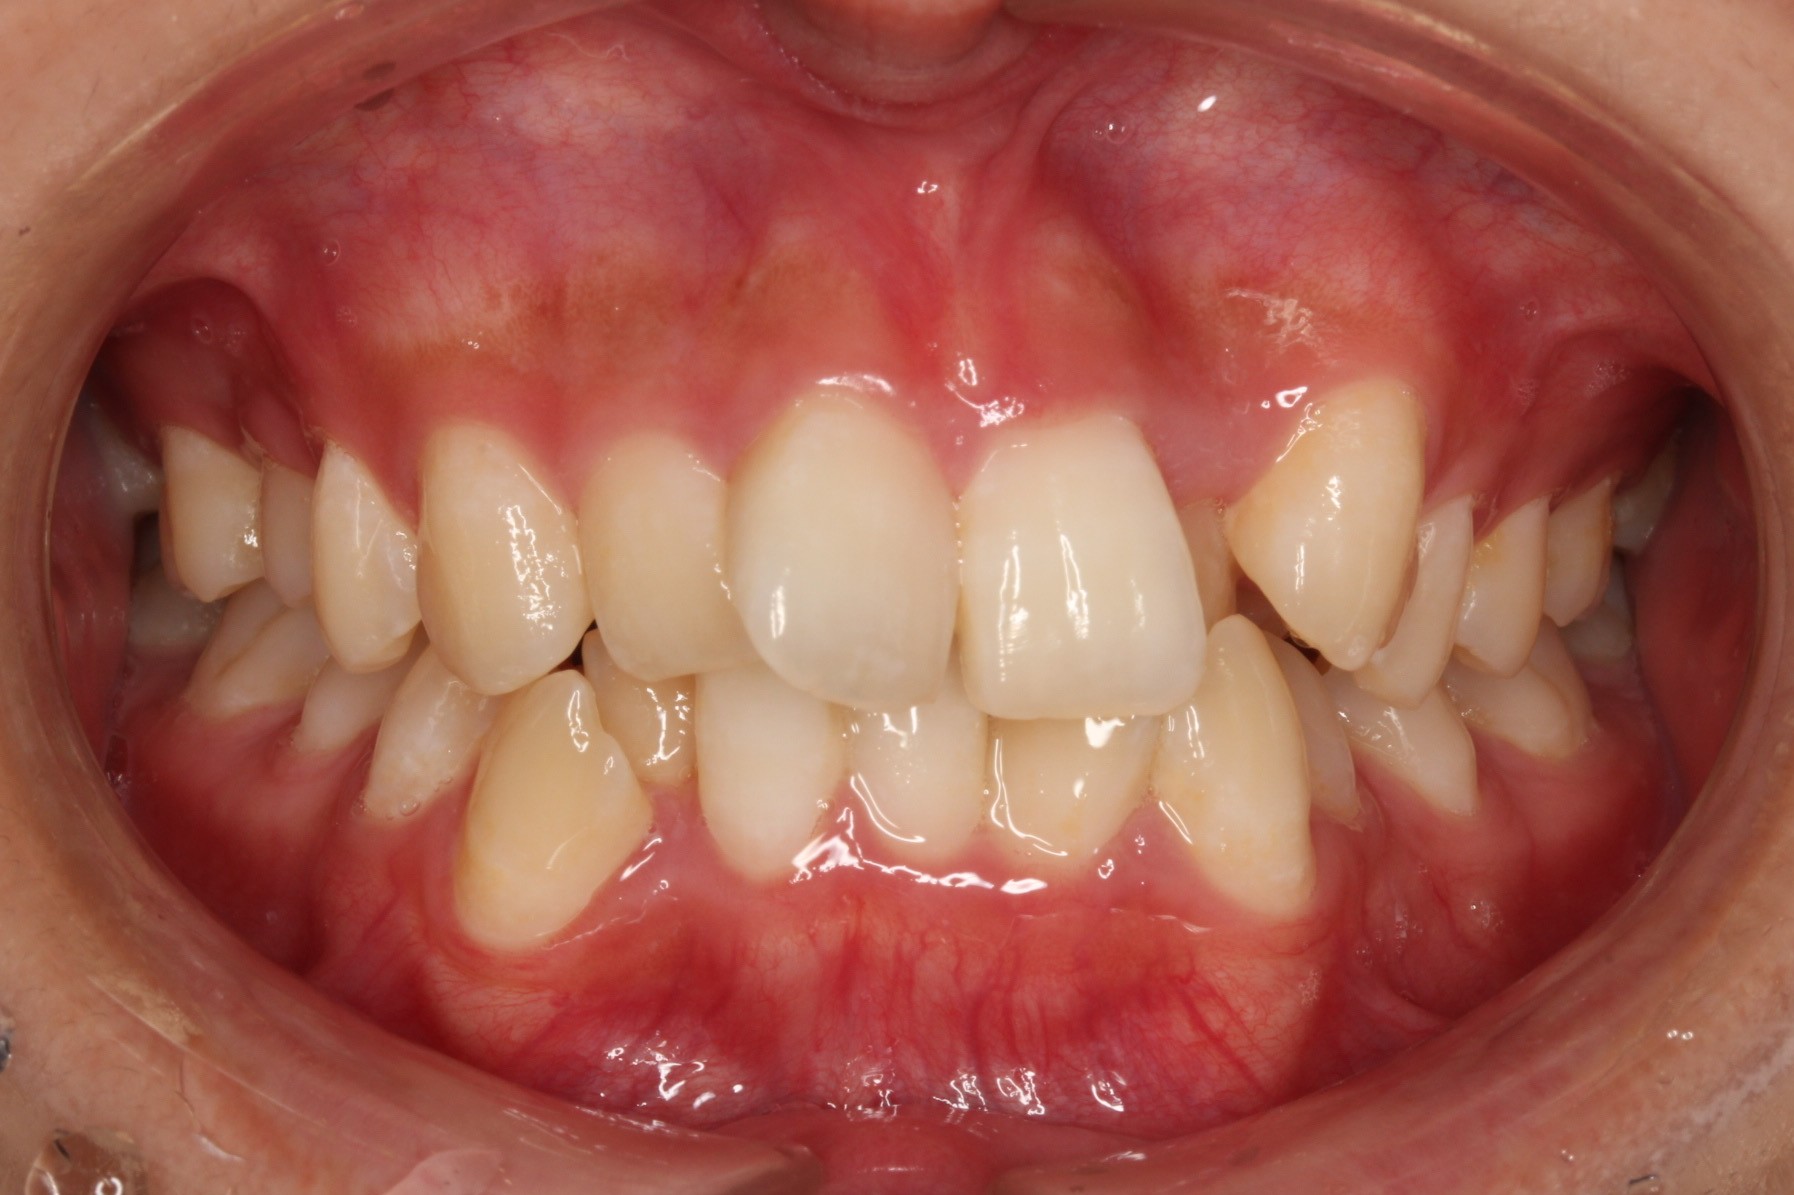

今回ご紹介する患者様は、上下のがたつきを気にされており、矯正検査後叢生Ⅰ級と診断いたしました。

矯正前に、上下小臼歯4本を抜歯いたしました。また、ワイヤー矯正後に、インビザラインで仕上げ矯正を行いました。

矯正術前:正面

| 主訴 | 上下のがたつきが気になる |

| 治療期間 | ・ワイヤー矯正:23カ月 ・インビザライン矯正:15か月 |

| 治療費用 | 1,100,000円(税込) |

| 治療内容 | 患者様は、上下のがたつきを気にされており、矯正検査後叢生Ⅰ級と診断いたしました。矯正前に、上下小臼歯4本を抜歯いたしました。また、ワイヤー矯正後に、インビザラインで仕上げ矯正を行いました。 |